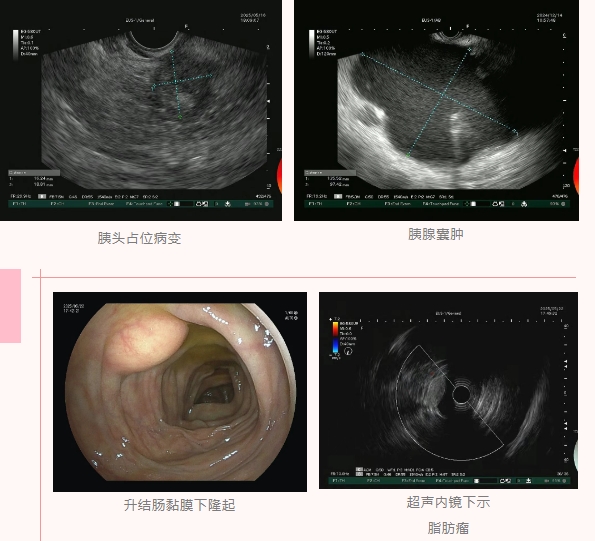

胰腺位于腹膜后,其占位性病变的病理活检难度较大,远不如胃肠道活检那般简便。胰腺癌的诊断往往需借助超声内镜引导下的穿刺,这一过程需穿透胃或肝脏等重要脏器,而周围解剖结构复杂、血管密集,不仅操作难度高,并发症发生风险也显著高于腹腔内器官穿刺,因此被视作难度最大的穿刺活检之一。

近日,一名中年男性因腹痛前往我院肝胆外科就诊,核磁共振检查显示其肝内外胆管扩张,胰腺头部疑似存在肿瘤样改变。由于胰腺位于腹膜后,虽核磁共振提示胰腺头部有占位性病变,但受胃肠道气体等因素干扰,想通过无创方式明确病变性质难度极大。

是直接为患者实施胰十二指肠切除术,还是继续进行病理活检?秉持谨慎手术的原则,肝胆外科医生建议进一步明确诊断——获取被誉为肿瘤诊断“金标准”的病理结果。经MDT多学科会诊讨论后,消化内镜中心团队决定为患者开展超声内镜引导下细针穿刺活检。

5月16日,消化内镜中心团队为患者实施无痛超声内镜检查,精准辨认病灶、瞄准目标,顺利完成胰腺头部病变的超声内镜引导下细针穿刺活检。整个操作一气呵成,患者全程无痛苦,麻醉复苏后也未出现任何不适,对治疗过程十分满意。

超声内镜引导下细针穿刺/活检术(EUS-FNA/B)的作用与应用

超声内镜引导下的细针穿刺/活检术(EUS-FNA/B)是一种相对新型的介入性内镜诊疗技术。通过内镜和超声扫描的结合,医生可以对患者体内特定部位病灶进行连续动态扫查,观察内部细微结构差异进行鉴别诊断。如有诊断需要,同时可以精准穿刺,获取组织或细胞样本,从而进行病理学检查,明确病变的性质和组织来源,为临床治疗提供准确的依据。这种技术在胰腺疾病、胆道疾病、壶腹部疾病、纵隔肿瘤和粘膜下肿瘤的诊断中具有重要作用,尤其对于那些在CT、核磁共振或PET-CT检查后仍较难定性或难发现的病例,EUS扫查及必要时的FNA/B能够提供更进一步的诊断依据。(来源:消化内科 颜蓉)